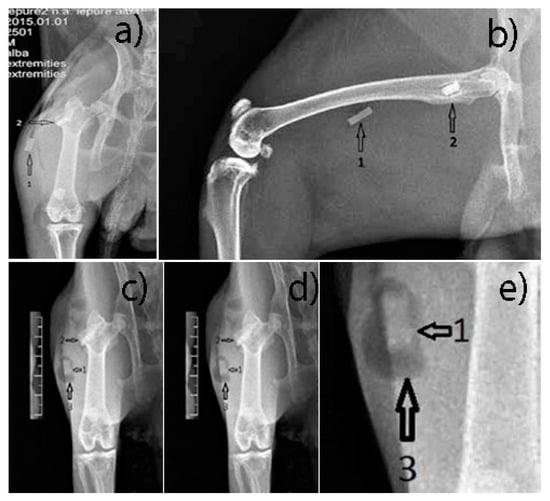

The muscle implant shows moderate changes in shape. The bone implant shows more advanced changes in shape. Transparent delimitation lines with bone tissue are not observed. Hydrogen bubbles have predominant development in the soft tissues (Figure 13).

Figure 13.

(a,b) Post-Operative X-ray, (c–e) 6 weeks post-operative X ray. 1—parallelepiped implant inserted into the thigh muscles; 2—parallelepiped implant inserted into the bone tissue, greater femoral trochanter; 3—hydrogen bubbles formed around the implant.